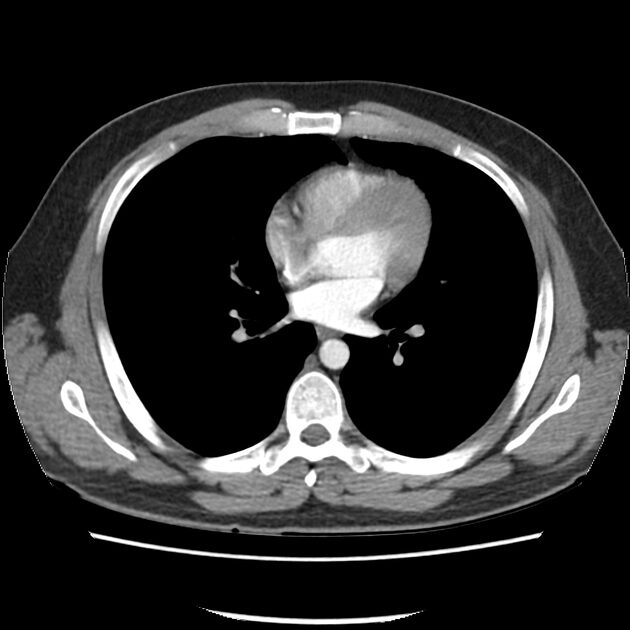

Wee Diagnostics has established a new & latest 128 Slice CT Scan Machine GE’s Revolution Maxima at MBS Hospital, Kota. GE Revolution Maxima is a new standard computed tomography, powered by artificial intelligence technology. For better clinical performance, Revolution Maxima has Clarity Imaging Chain consists of Clarity Detector, DAS, PerformixTM40 Plus X-ray Tube and ASiR-VTM / ASiRTM reconstruction (Option) and delivers high resolution imaging to meet various customer needs in real clinical situations. Clarity Imaging Chain delivers higher spatial resolution, lower noise, or less-artifact.